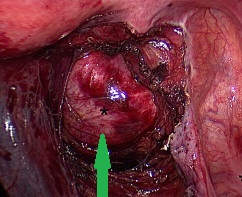

The cystic part of the tumor contained a pale-yellow, thin fluid, odorless and sterile (Courtesy Dr. V. Penopoulos)